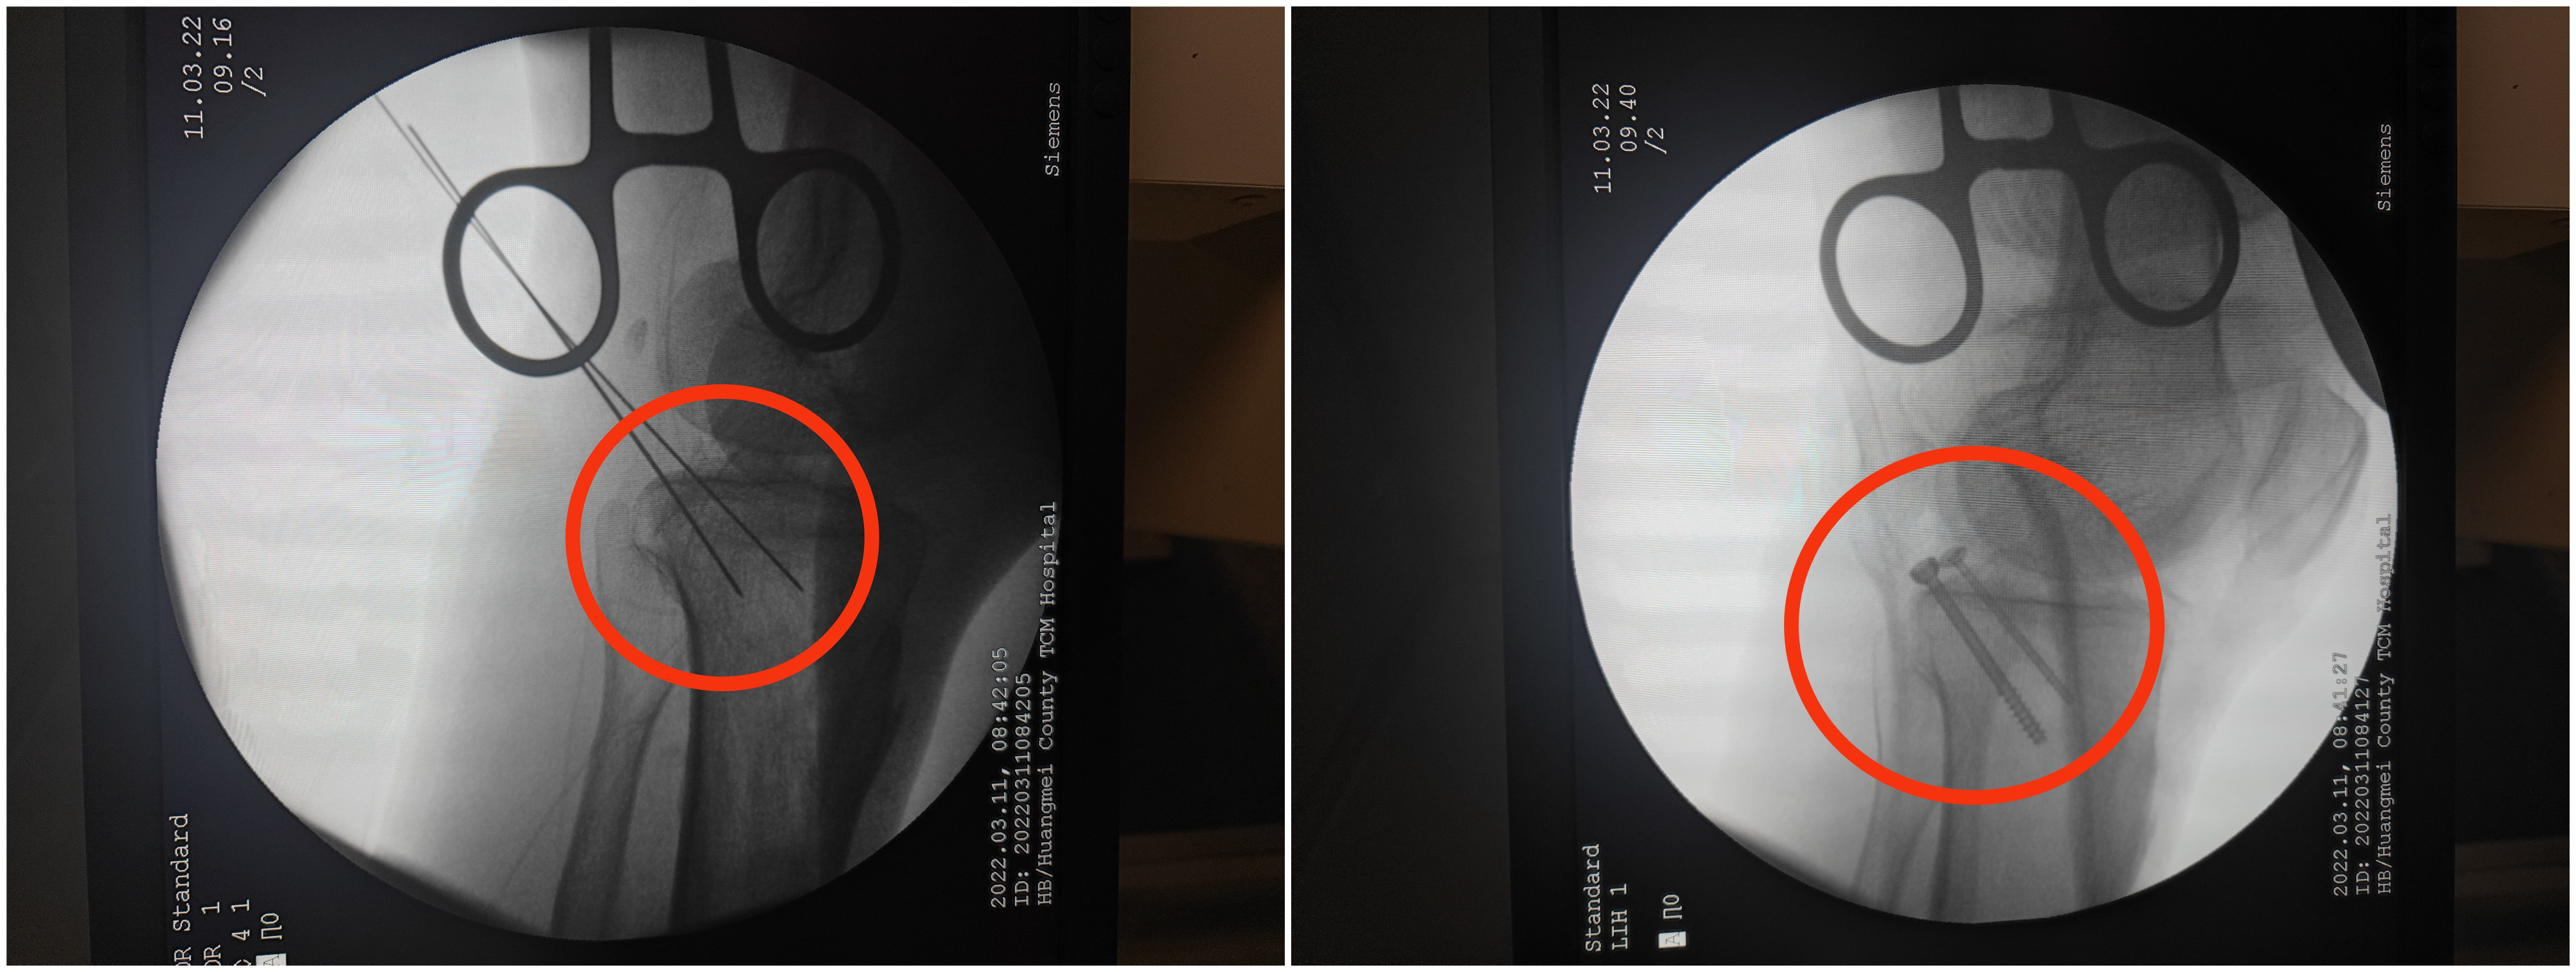

红色圆圈内可以看见移位的骨块复位好后,我们用两枚空心螺钉固定